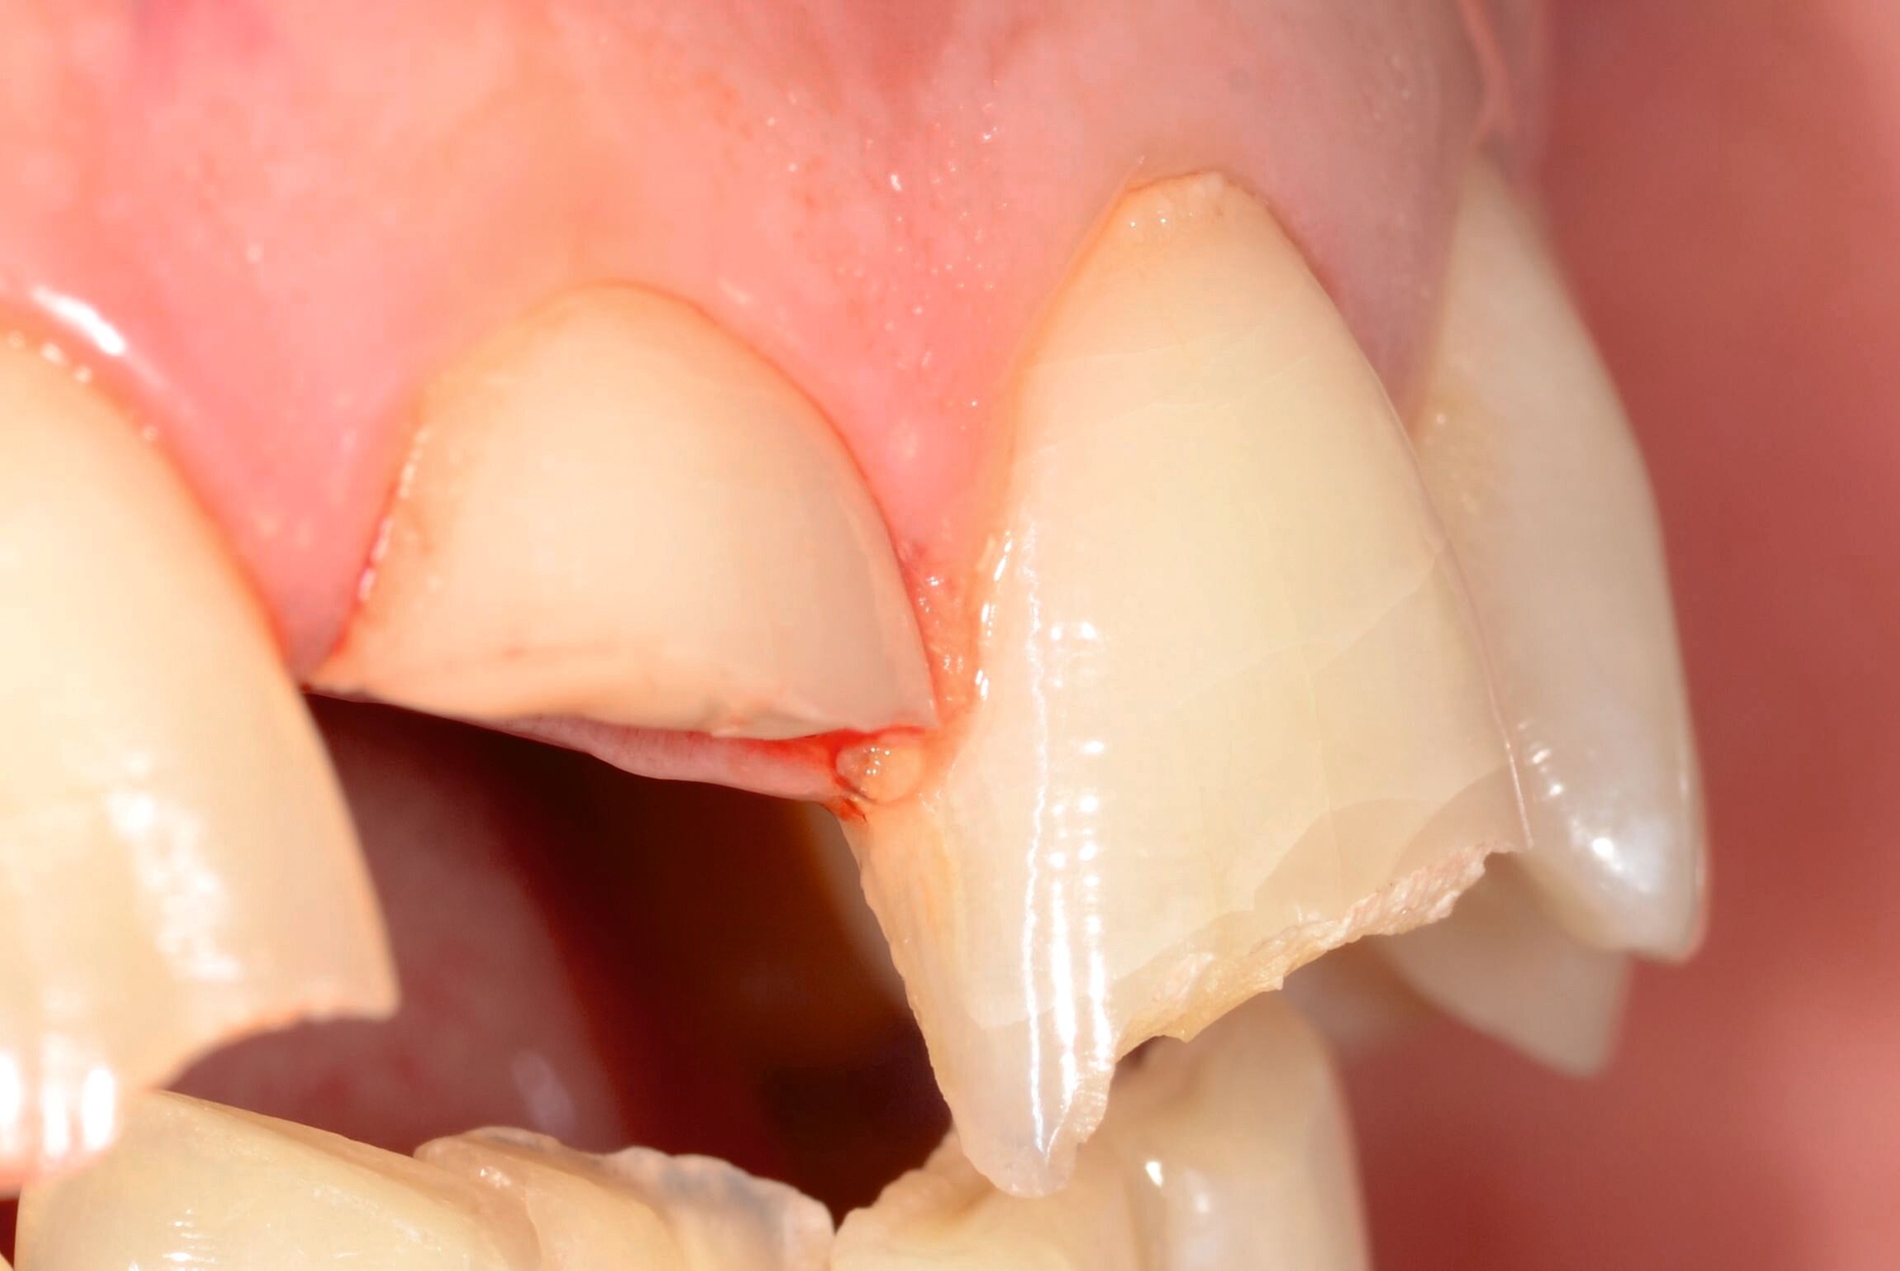

Zur Vorbereitung ist eine Rehydrierung des etwa drei Stunden trocken gelagerten Fragments, beispielsweise im Drucktopf für 60 Minuten, notwendig. Dadurch werden bestmögliche Voraussetzungen für den adhäsiven Verbund sowie eine ideale Farbanpassung geschaffen. Vor der Wiederbefestigung des Fragments werden außerdem der Sulkus des Zahnes 11 auf verbliebene Teilfragmente und der Zahn auf mögliche Wurzellängsfrakturen untersucht (Zahnfilm-Abbildung 1e). Nach Infiltrationsanästhesie wird der subgingivale Defekt mithilfe einer Gingivektomie und anschließender Blutstillung vorsichtig dargestellt, wodurch eine ausreichende Trockenlegung für das adhäsive Reattachment erzielt werden kann. Das Fragment wird anschließend mit Aluminiumoxid (50 µm) abgestrahlt, die Frakturfläche an Zahn 11 sowie das Fragment werden mit Phosphorsäure konditioniert.

Die adhäsive Konditionierung erfolgt durch ein Ein-Schritt-Adhäsivsystem, das nach dem Auftragen nicht polymerisiert wird, um die exakte Passung des Fragments nicht zu beeinträchtigen. Anschließend wird die Frakturfläche dünn mit einem dualhärtenden Befestigungskomposit bestrichen, anschließend das Fragment repositioniert. Nach vorsichtiger Entfernung der Überschüsse, insbesondere im Sulkus, wird lichtpolymerisiert, abschließend die Okklusion überprüft und der Zahn 11 poliert (Abbildung 2).